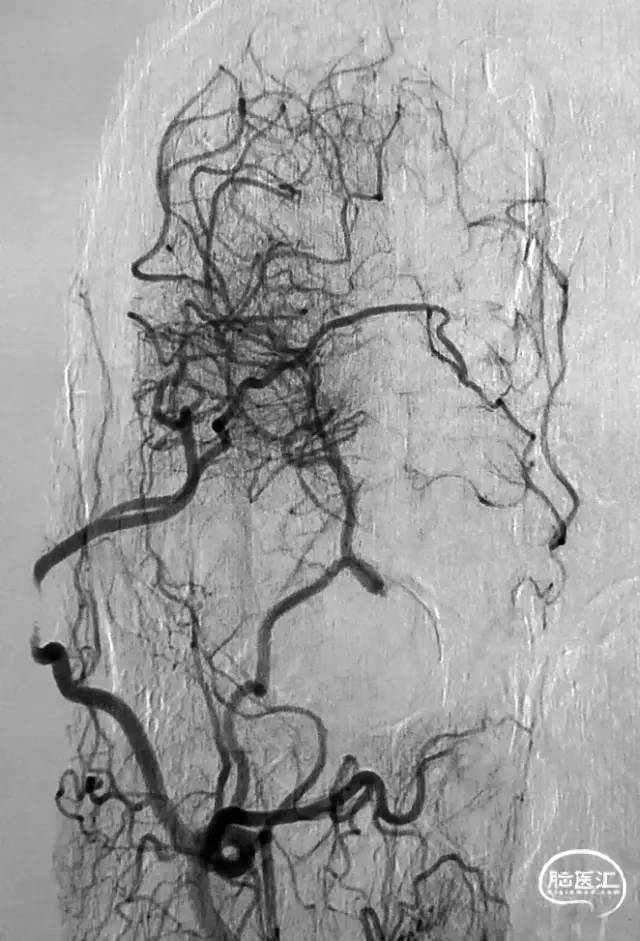

图1 从大脑后动脉(PCA)到大脑前动脉(ACA)的软脑膜侧支;A. 椎动脉注射侧位图显示ACA和PCA区域之间的逆行血流(PCA→ACA顶枕支)延伸到皮质边界区;B. 经后胼胝体周动脉经中央沟的血供。[7]